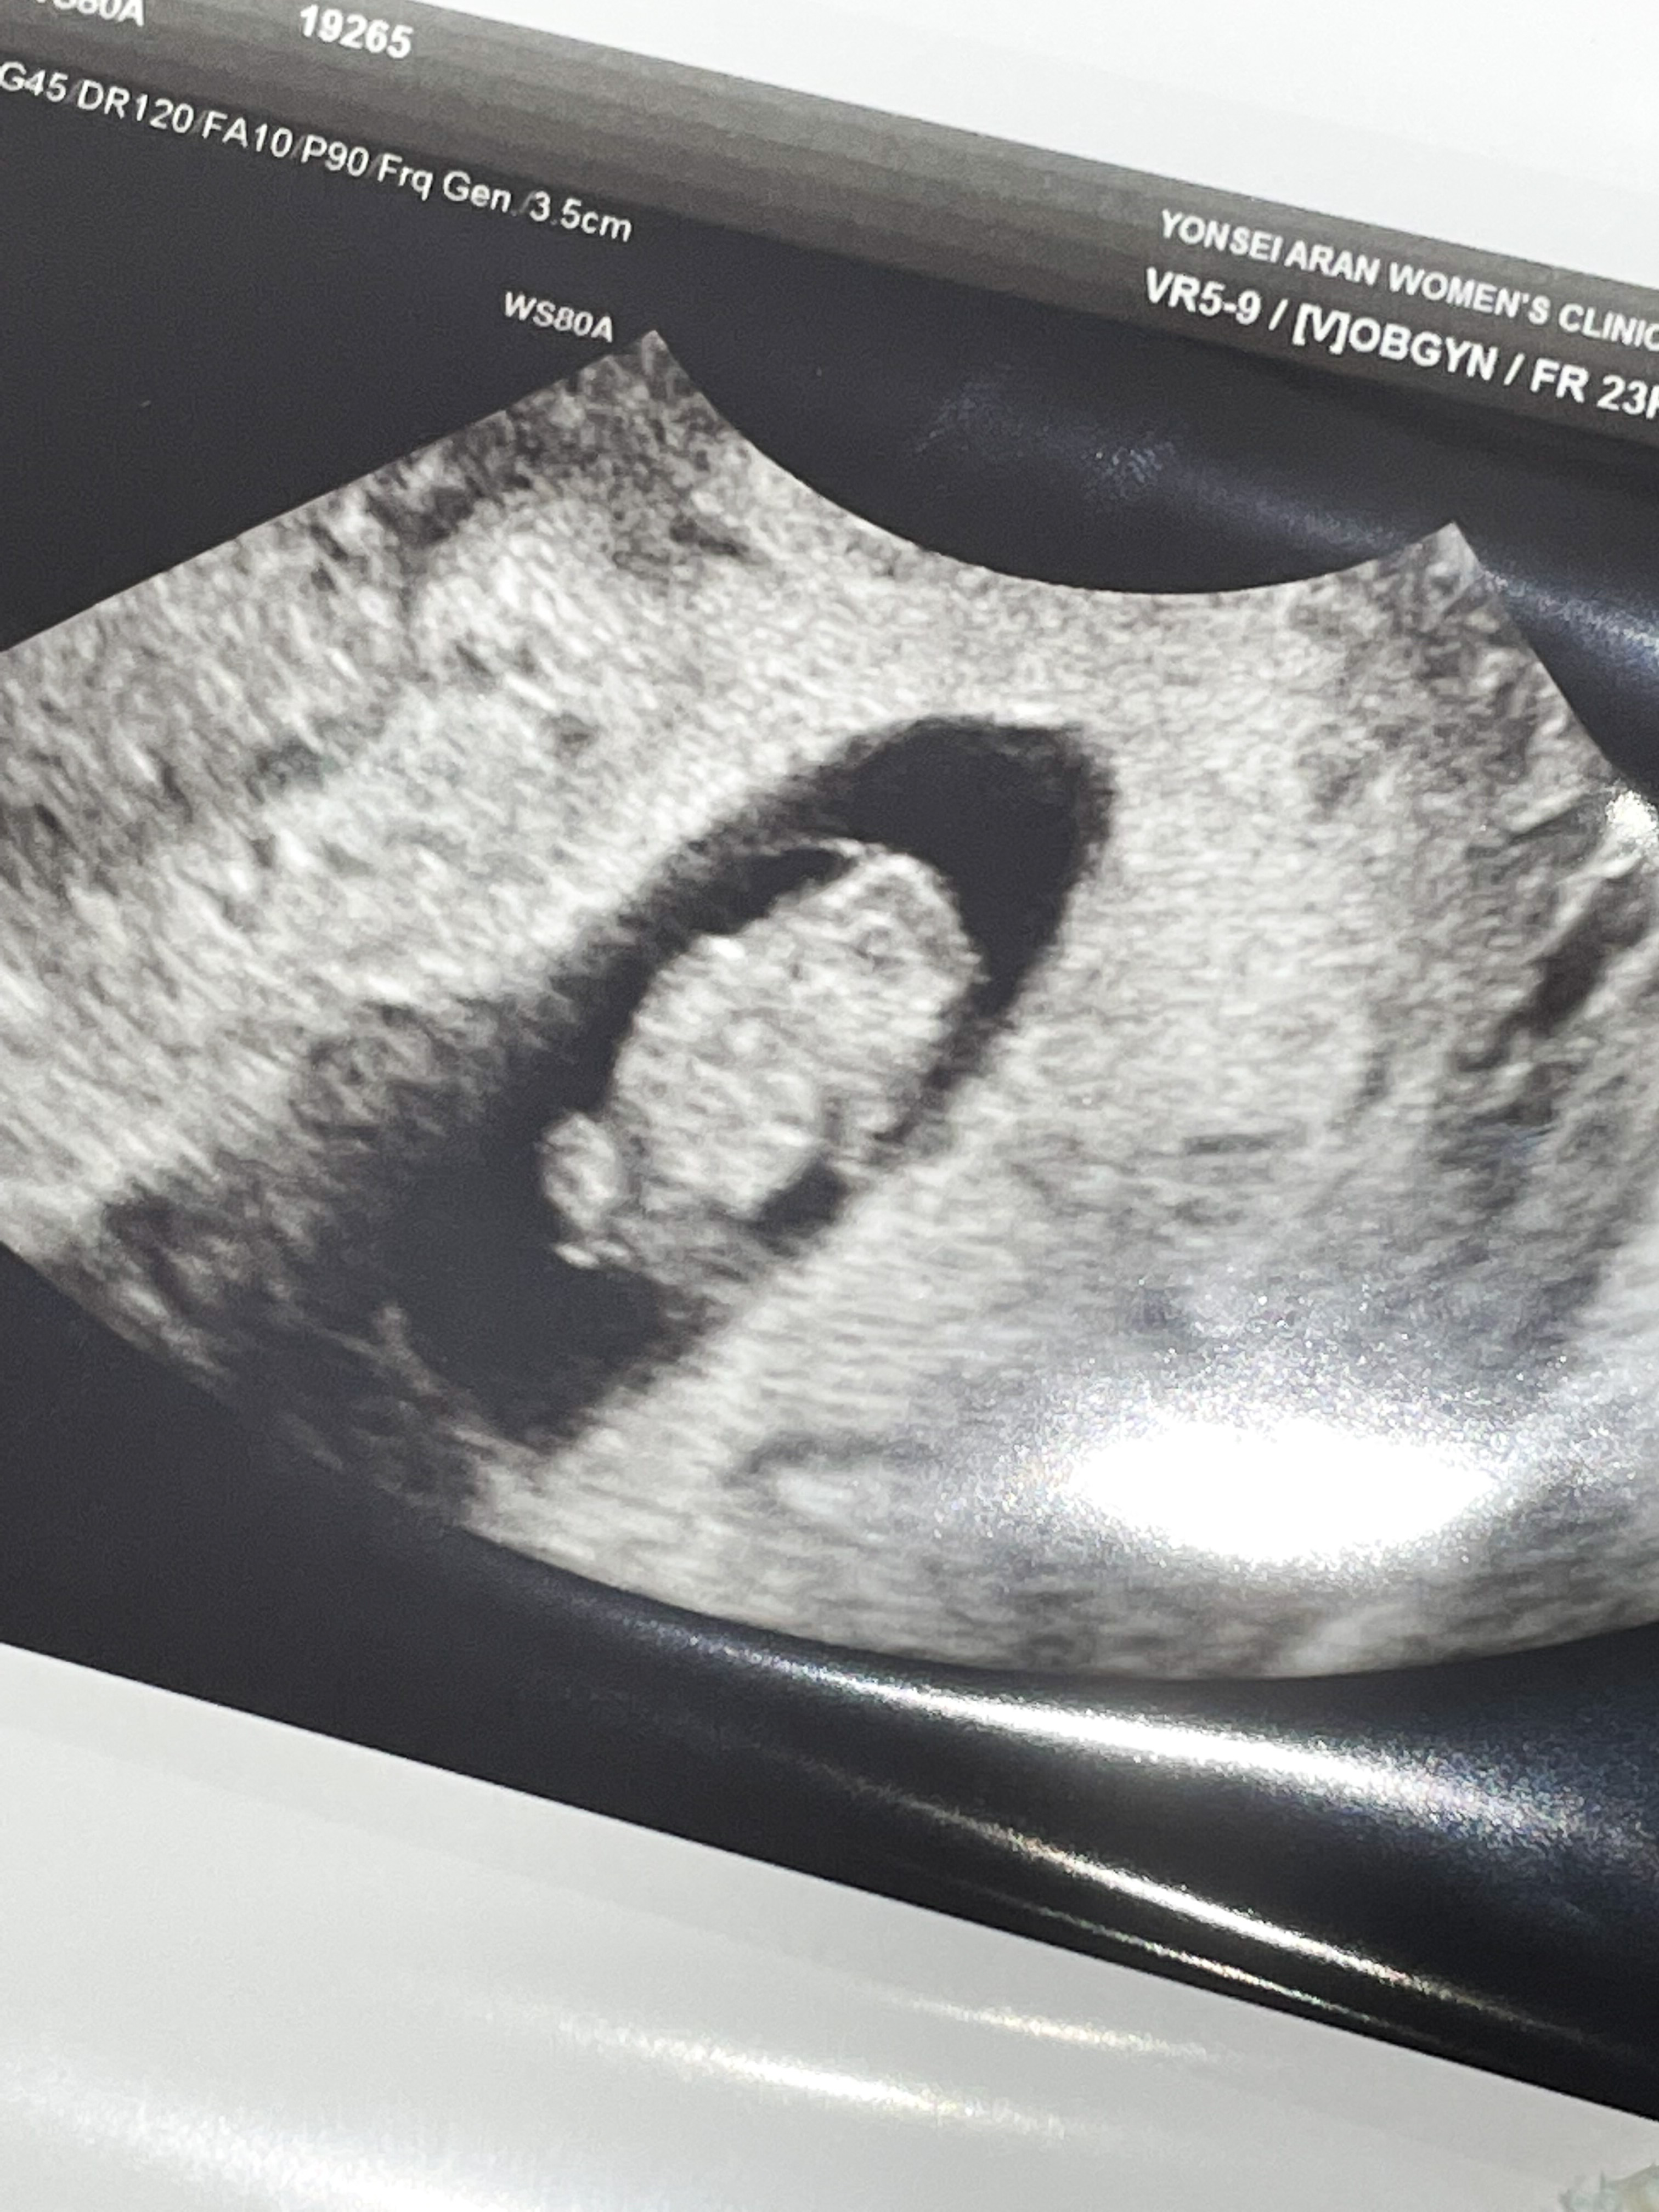

8주 1일

입덧약 처방 받으러 간 김에 초음파도 한 번 봤다.

막대기 같이 생겼던 아기가 어느덧 통통해졌고 팔다리까지 있었다.

쌤이 젤리곰이라고 너무 귀엽다고 하셨는데,

내 눈에는 물개 같았다.

심장도 잘 뛰고 있었다.

뇌 쪽이 구멍이 뚫려 있었는데 정상이라고 하셨다.